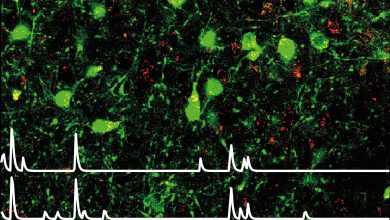

Os neurônios sensores de leptina no hipotálamo lateral (de cor verde) ajudam a superar a ansiedade para permitir o comportamento…